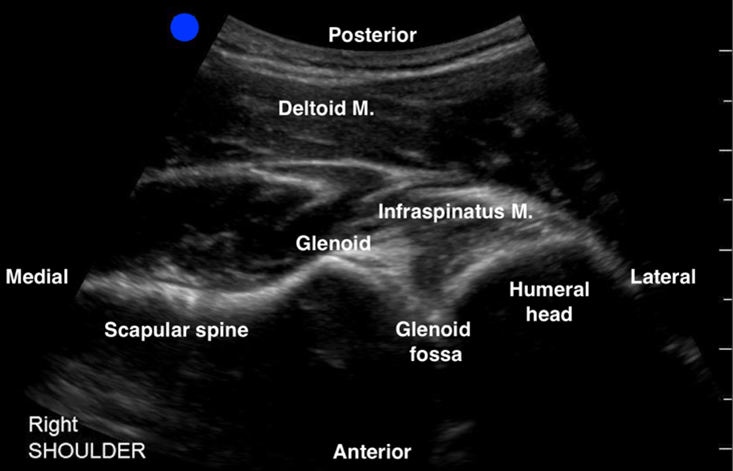

- The scapular spine can be identified as a hyperechoic line with a posterior shadow. Note that the deltoid and the infraspinatus muscles can be seen above the scapular spine (See Figure 1).

- Continue sliding the probe laterally along the scapular spine towards the glenohumeral joint (GHJ), until visualizing the glenoid fossa which is closely followed by the humeral head (See Figure 1). Positioning the glenoid fossa and the GHJ in the center of the screen while adjusting the depth, will result in a better image quality. Asking the patient to externally and internally rotate the affected shoulder will aid in identifying the humeral head (See Figure 2).

Figure 1: Normal right shoulder